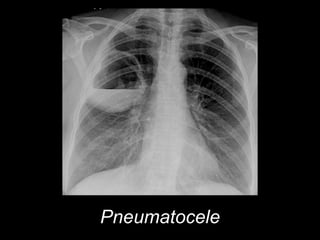

Pneumatocele